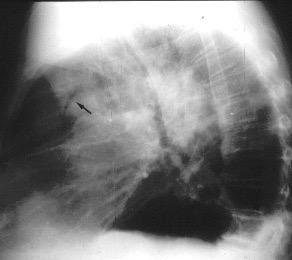

Raro. (2-9% de los T. tímicos). Asintomático. Contiene grasa (hasta 90%) y tejido timico (10-33%). Pueden ser muy grandes y confundirse con cardiomegalia. La tomografía “clásica” muestra los límites de la silueta cardiaca. (flechas)